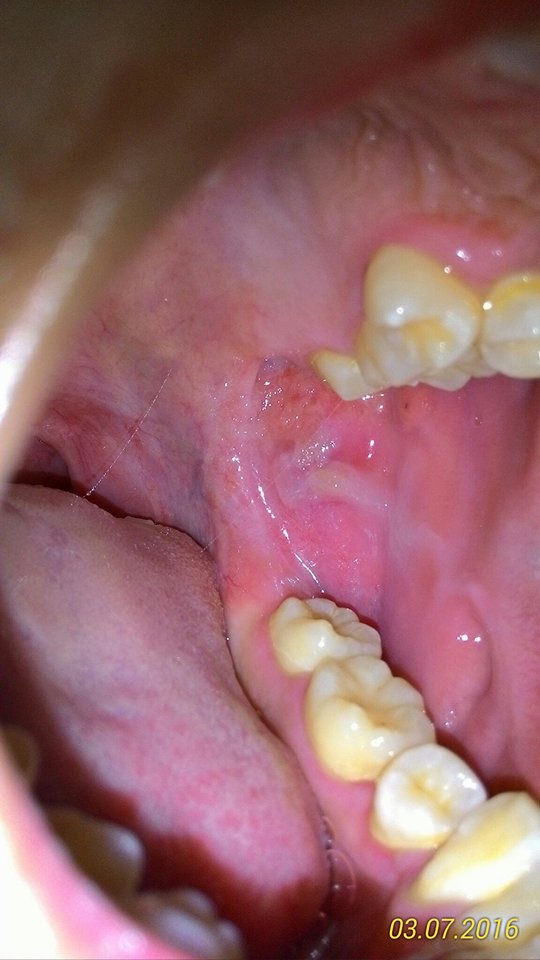

อาการ -เจ็บที่แผล กลื่นน้ำลายเจ็บคอ กลื่นอาหารยาก -เป็นนานเกิน3สัปดาห์ เป็นแล้วกลับมาเป็นใหม่แบบเปลี่ยนที่ -เป็นแผลในช่องปากบ่อย (แผลเก่าหายได้ไม่นานสัปดาห์ต่อมาเป็นอีก) -ลักษณะของแผลเป็นวงกลมเล็กในวันแรกๆ และขยายใหญ่ขึ้น สีของแผลเป็นสี ขาว-เหลือง -ปากมีเส้นสีขาวตรงกระพุ้งแก้มเป็นมาหลายปีไม่หาย กระพุ้งแก้มเป็นหลุมของแผลเก่าที่เนื้อยังไม่เรียบเสมอกัน ขอโทษด้วยครับคุณหมอผมพยายามนึกอาการและเรียบเรียงให้คุณหมอ http://haamor.com/media/images/webboardpics/8c36e-28431.jpg http://haamor.com/media/images/webboardpics/8c36e-28431-2.jpg http://haamor.com/media/images/webboardpics/8c36e-28431-3.jpg คุณหมอพอจะวินิจฉัยเบื้องต้นได้มั้ยครับ ว่าเกิดจากอะไร ผมกังวลและกลัวจะเป็นไรร้ายแรงมากๆครับ ขอบคุณครับคุณหมอ สวัสดีครับ

รูปภาพเพิ่มเติมครับ แต่ละรูปเป็นแผลคนล่ะที่กันในแต่ล่ะเดือนรูปที่ 3 (รูปนี้)เป็นตอน ประมาณเดือน กุมภาพันธ์ประมาณ กลางๆเดือนเป็นข้างซ้าย แล้วพอมาเดือน มีนาแผลใหม่ก็ไปเป็นทางด้านขวาลักษณะคล้ายๆ กันเป็นแบบในรูปครับ ขอโทษคุณหมอด้วยครับที่ตั้งกระทู้ถาม อาจทำให้เกิดความสับสน ผมพยายามให้ข้อมูลให้มากที่สุดขอบคุณครับคุณหมอ |

14 พฤษภาคม 2559 16:09:46 #3 อาการเพิ่มเติม (ภาพแรกบนสุด) -แผลมีเลือดออก -เจ็บ ปวดแผล ปวดร้าวไปถึงหูข้างซ้าย(เจ็บหูเวลากลืนน้ำลาย รู้สึกปวดหูนิดๆอยู่ตลอดเวลา)แผลในปากเป็นข้างซ้ายของลิ้นไก่